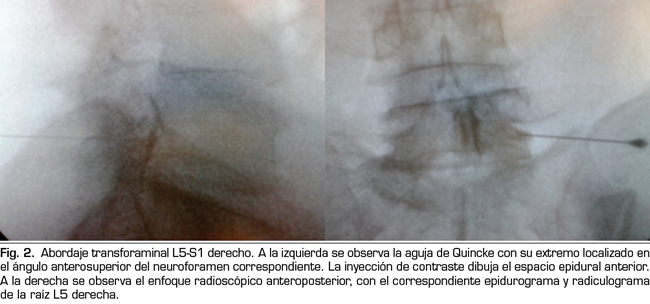

Los procedimientos fueron realizados en sala de operaciones. Con el paciente en posición decúbito ventral se colocó una vía venosa periférica. La asepsia se efectuó con clorhexidina alcohólica y la anestesia local con lidocaína al 0,5 %. En la técnica interlaminar parasagital se utilizaron agujas de Tuohy números 18, 3½ o 4¾ pulgadas según la complexión física del paciente. Con enfoque radioscópico anteroposterior, se introdujo la aguja en los espacios interlaminares, L4/L5 o L5/S1, utilizando la técnica en visión túnel, parasagital homolateral del lado correspondiente al dolor radicular (Figura 1). Se realizó pérdida de resistencia con suero fisiológico. En el enfoque lateral se administró una inyección de 4 ml de contraste (Omnipaque®) y se consignó la presencia de epidurograma anterior, posterior o ambos (Figura 1). En el enfoque anteroposterior se consignaron las características del radiculograma y del epidurograma (Figura 1). Luego se administró un frasco de betametasona (12 mg de una mezcla de fosfato y acetato de betametasona, en 2 cc de solución) más 3 cc de lidocaína al 0,5 % (total 5 cc de solución). Se evaluó la calidad técnica del bloqueo con elementos clínicos como la presencia de parestesias o dolor concordante durante la inyección, y datos radiológicos como la presencia de radiculograma y de epidurograma anterior (Figura 1). En el grupo tratado con betametasona por vía epidural transforaminal se utilizaron agujas de Quincke números 22, 3½ o 4¾ pulgadas con enfoques radiológicos oblicuo, lateral y anteroposterior. El punto objetivo en posición oblicua fue la zona subpedicular, en enfoque lateral el ángulo anterosuperior o techo del neuroforamen, en el llamado triángulo de seguridad en el enfoque anteroposterior (Figura 2). La inyección de contraste fue equivalente a la realizada en el grupo interlaminar, debiéndose obtener radiculograma y epidurograma tras la inyección (Figura 2). La solución de betametasona fue la misma que la utilizada en el grupo interlaminar, inyectándose la totalidad de la solución por el neuroforamen elegido, o la mitad de la solución en cada neuroforamen cuando por criterios clínicos se decidió la inyección en dos niveles.

En 21 de los 26 procedimientos realizados por el acceso interlaminar parasagital se evaluó la calidad técnica de la inyección epidural de esteroides. En 15 (71 %) se obtuvo epidurograma anterior, esto es, alcance de la solución en la cara ventral del espacio (Figura 1 izda.); en 17 (85 %) el paciente refirió dolor o parestesias en el territorio radicular durante la inyección, y en 12 (60 %) se observó radiculograma junto a la imagen característica de epidurograma.